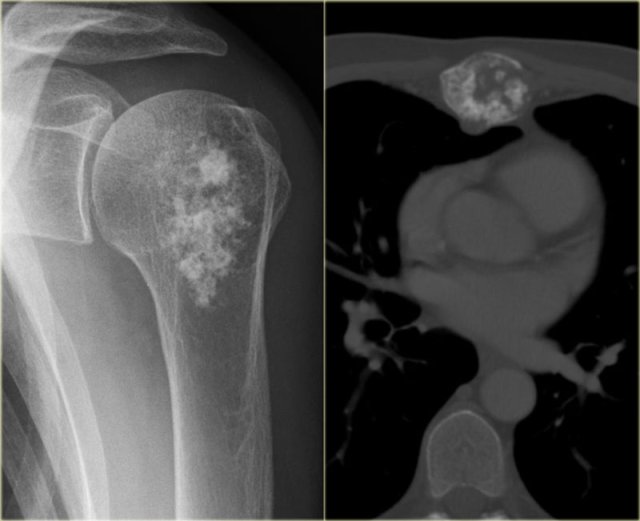

Chondrosarcoma in humeral head and sternum Chondrosarcoma in humeral head and sternum

Here two other lesions in different patients that proved to be chondrosarcoma.

The sclerotic lesion in the humeral head could very well be a benign enchondroma based on the imaging findings.

Symptoms are usually absent, however, in adult patients with a chondroid lesion in a long bone, particularly of larger size, always consider low-grade chondrosarcoma.